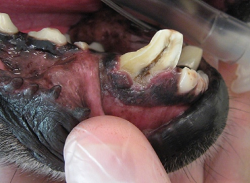

- Toothless cavaliers are disabled dogs. -- October 29, 2025

- Giving your cavalier a bone will not prevent or treat dental disease and may fracture teeth. -- August 24, 2022

- The accordion-muzzled cavalier King Charles spaniel. -- December 12, 2013